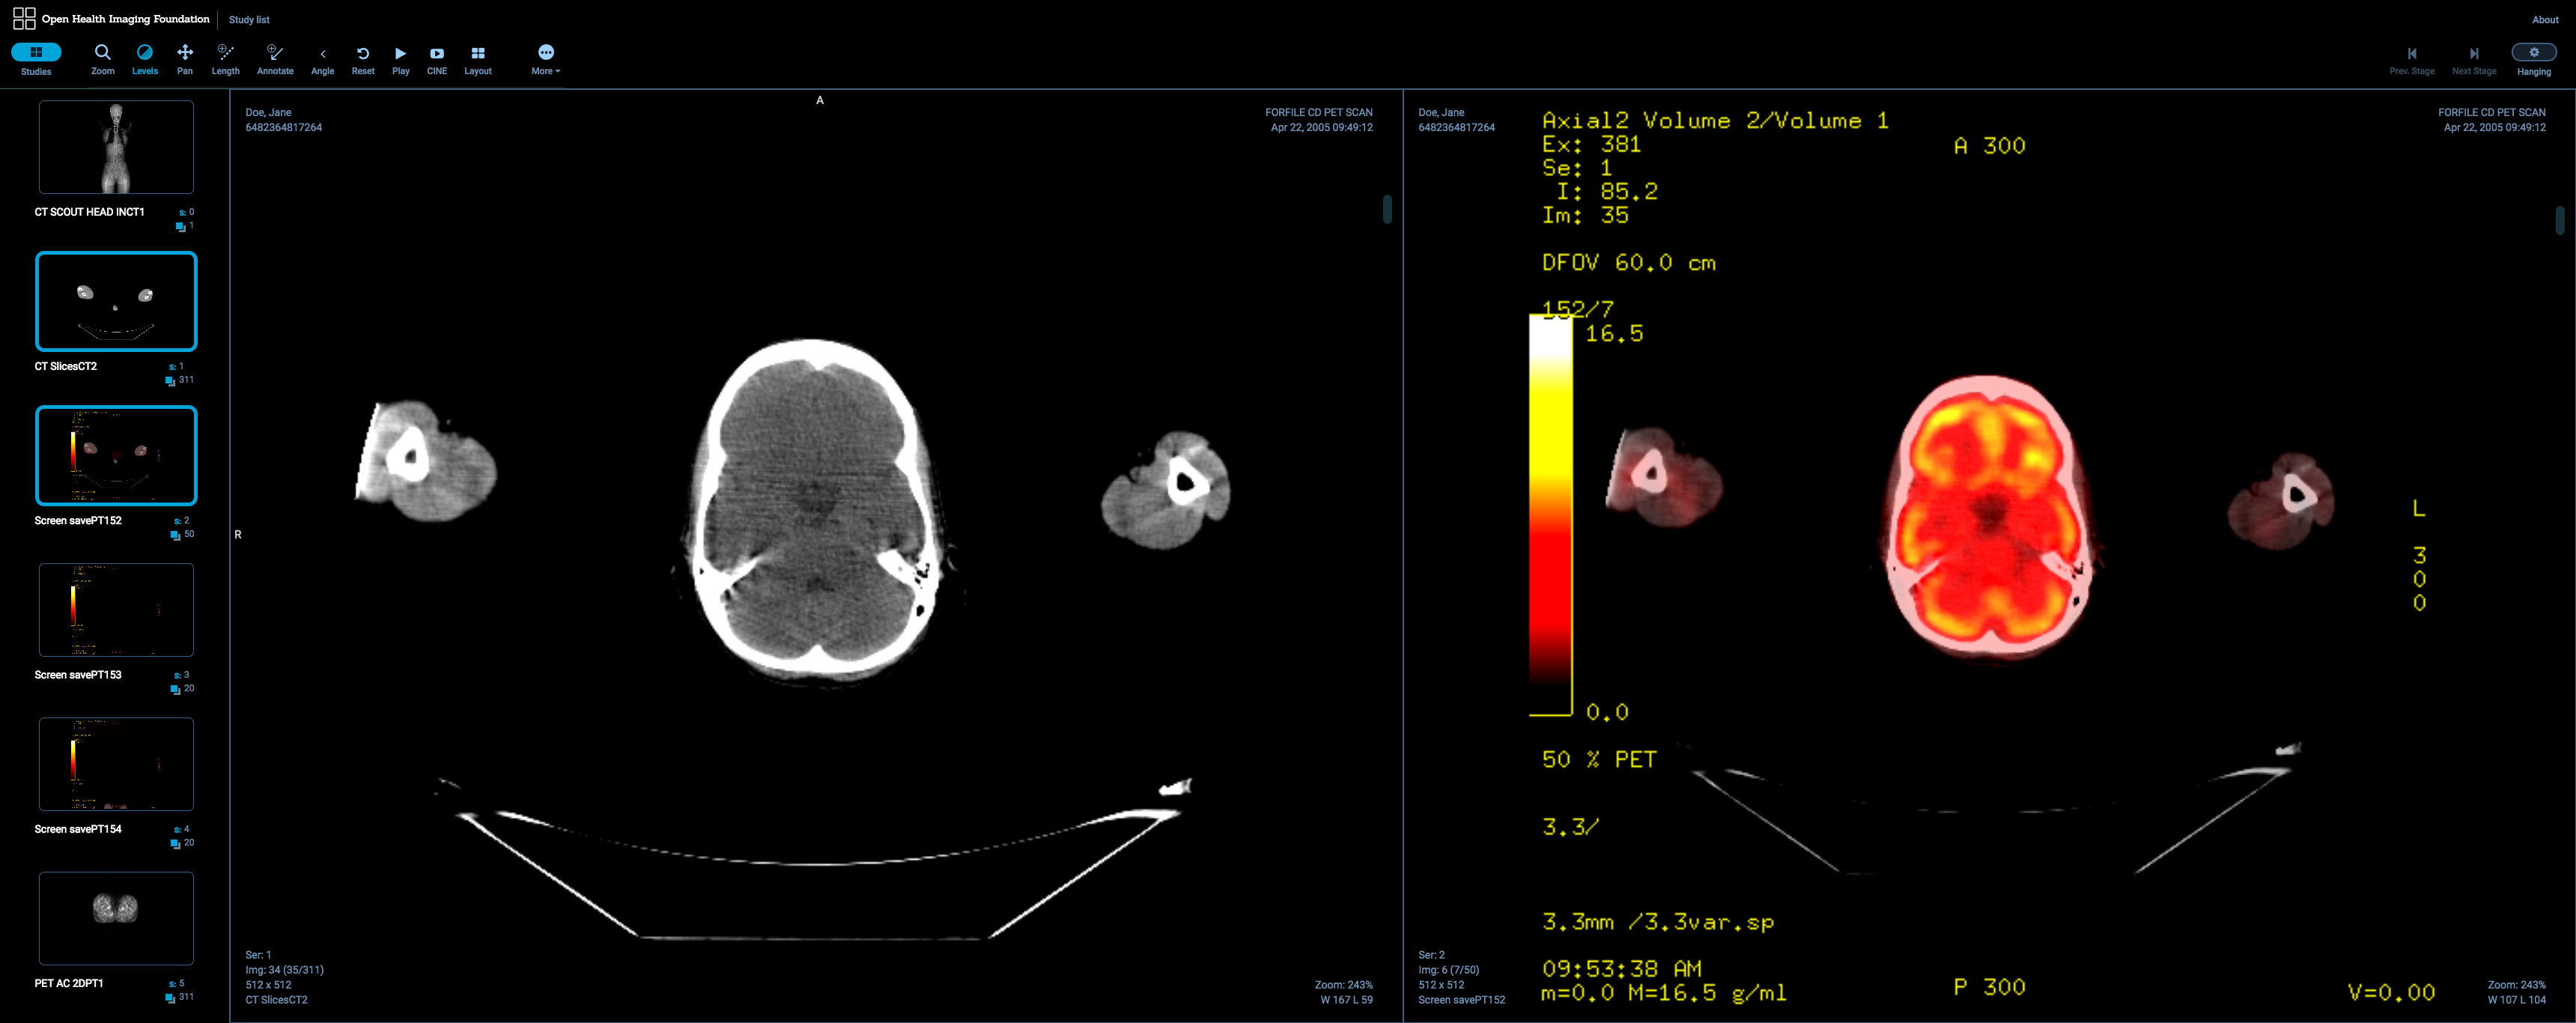

The OHIF Viewer: A general purpose DICOM Viewer (demo)

The Open Health Imaging Foundation intends to provide a simple general purpose DICOM Viewer which can be easily extended for specific uses. The primary purpose of the OHIF Viewer is to serve as a testing ground for the underlying packages and the Cornerstone family of libraries.